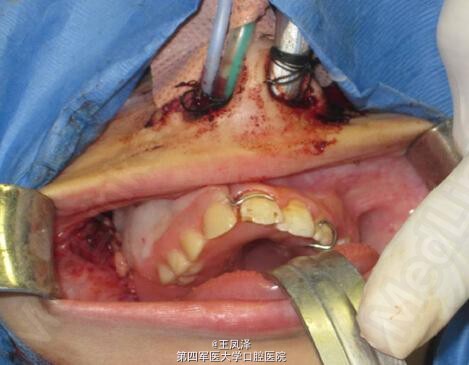

患者女,9 岁,发现右侧上颌骨无痛性肿块 3 个月余。查体见右侧上颌骨明显肿胀,质硬,不可活动,触之无疼痛感,约 3 cm× 2 cm 大小。肿块自右侧颊部向右侧腭部膨隆,右侧上颌牙齿移位,I 度松动。余未见明显异常